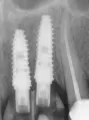

У меня такая ситуация: поставили два импланта, но близко и криво. Не знаю, удалить один или нет. Что посоветуете? Вместо двух зубов получается один зуб, якобы с двумя корнями. Как это?

Формирователи не вместились на одном уровне, одна низкая, другая повыше. Одним словом, плохо сделали. Еще не знаю зачем-то подрезали десну. Якобы так надо.

Имплантаты могут иметь допустимый градус наклона.

Не переживайте, существуют разные абатменты, а также индивидуальные, которые позволят выровнять коронку в зубном ряду.